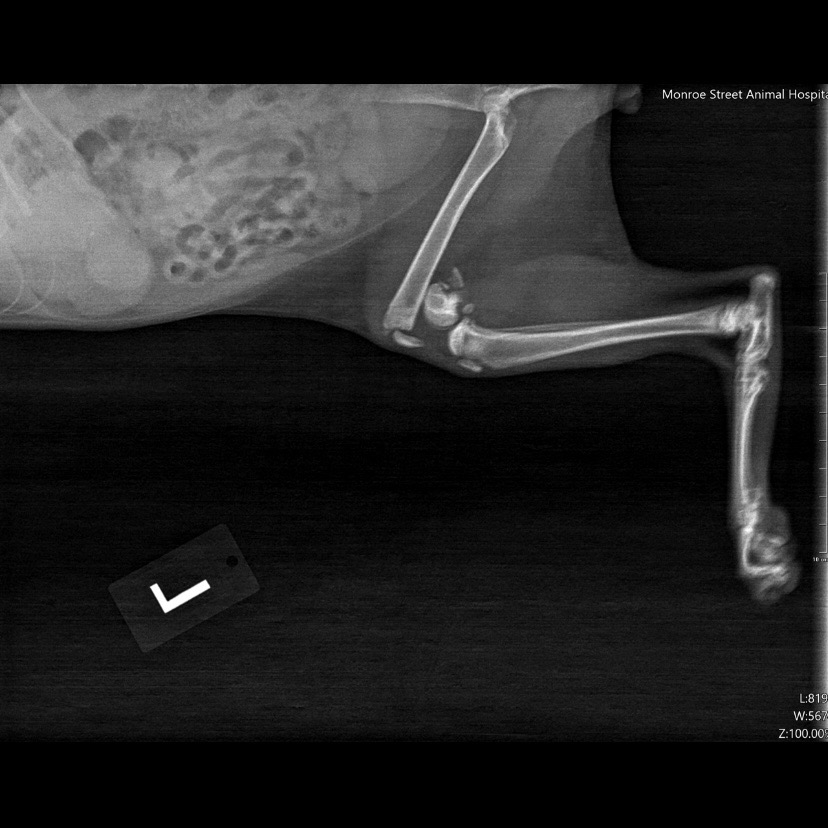

Imaging Services: Digital Radiographs and Ultrasound

Some answers require more than lab work. That’s where our imaging capabilities come in. With digital x-rays and ultrasound technology available onsite, our veterinary team can visualize internal organs, bones, and soft tissues in great detail.

Digital Radiography (X-rays):